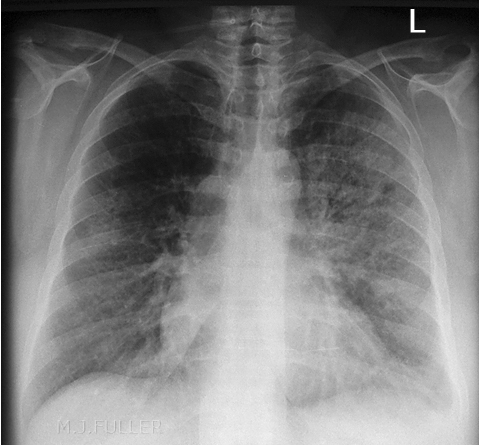

In radiological studies ________ _______ presents as increased attenuation of the lung parenchyma causing obscuration of pulmonary vessels, without significant loss of volume, in the segment(s) affected. Air bronchograms can also be found

Lung Consolidation

(right lower lung consolidation)